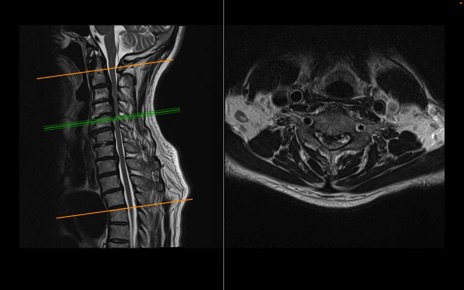

頚椎MRI

T2WI(横断像)

T2WI(矢状断像)